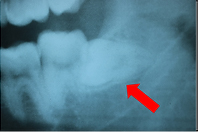

下の写真は、親知らずが横向きに生えていて隙間があります。

下の写真は、その隙間に食べかすが入ってしまっています。

この隙間は下の方が深歯ブラシが届かず、このままでは親知らずと手前の歯が2本とも虫歯になってしまうので抜いたほうが良いケースです。